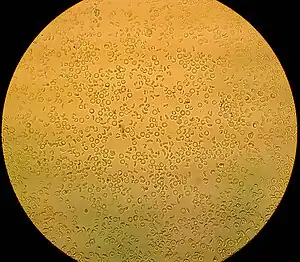

- Hematuria microscópica: el color de la orina es normal (amarilla), pero el examen de sangre en la orina es positivo. Hay pequeñas cantidades de sangre, visibles solo por uroanálisis o por un microscopio óptico. Aunque es posible que la tira química para el examen de la orina de falsos positivos, que son el resultado de, entre otros, la presencia de hemoglobina o mioglobina.

Los glóbulos rojos pueden proceder de los glomérulos renales. En este caso se someten a cambios durante el periodo de transición dentro de los túbulos renales, por lo que en el examen microscópico del sedimento urinario se ven hematíes mal conservados.[4] En este caso la hematuria glomerular por lo general es consecuencia de un daño al glomérulo, tal como una glomerulonefritis:

Los glóbulos rojos de los riñones pueden unirse entre sí y formar cilindros de sangre, lo que suele ser patognomónico de la hematuria glomerular y, por tanto, de la glomerulonefritis. El diagnóstico se basa en el interrogatorio que detecta las características del sangrado, la ecografía renal, que logra excluir otras causas, las características de los glóbulos rojos en el momento del examen microscópico del sedimento urinario. Un análisis más profundo puede requerir de biopsia renal.

Una causa igualmente rara de hemorragia es la necrosis de las papilas renales, fundamentalmente por el abuso de analgésicos y la anemia drepanocítica.[5] En los casos de ruptura de los quistes, el cáncer renal y la necrosis papilar, las células no suelen ser objeto de modificaciones durante el paso por los túbulos renales y, por tanto, normalmente se ven glóbulos rojos bien conservados bajo el microscopio.

El diagnóstico de hematuria debe hacerse por examen del sedimento de la orina, centrifugando la muestra recogida de inmediato después de la micción matutina. Normalmente, no se observan más de 2 hematíes por campo microscópico (a gran aumento).[9]